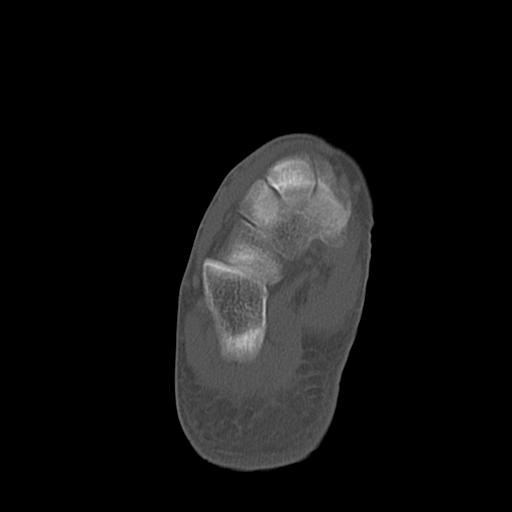

49554 3/13 膝 4R 3/16 4R 1/18 2R 78歳男性 膝蓋骨骨折